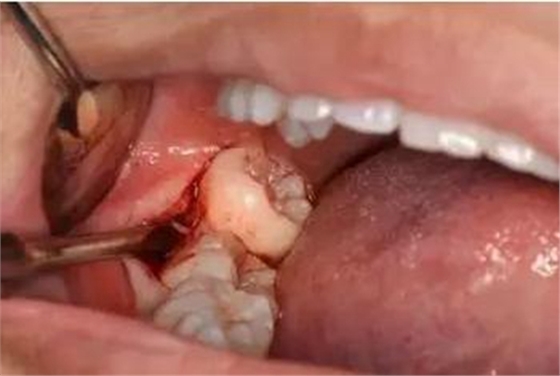

圖13.清理牙槽窩、對(duì)位傷口

圖14.僅在遠(yuǎn)中縫合兩針,不宜太緊。

圖15.拔除的48